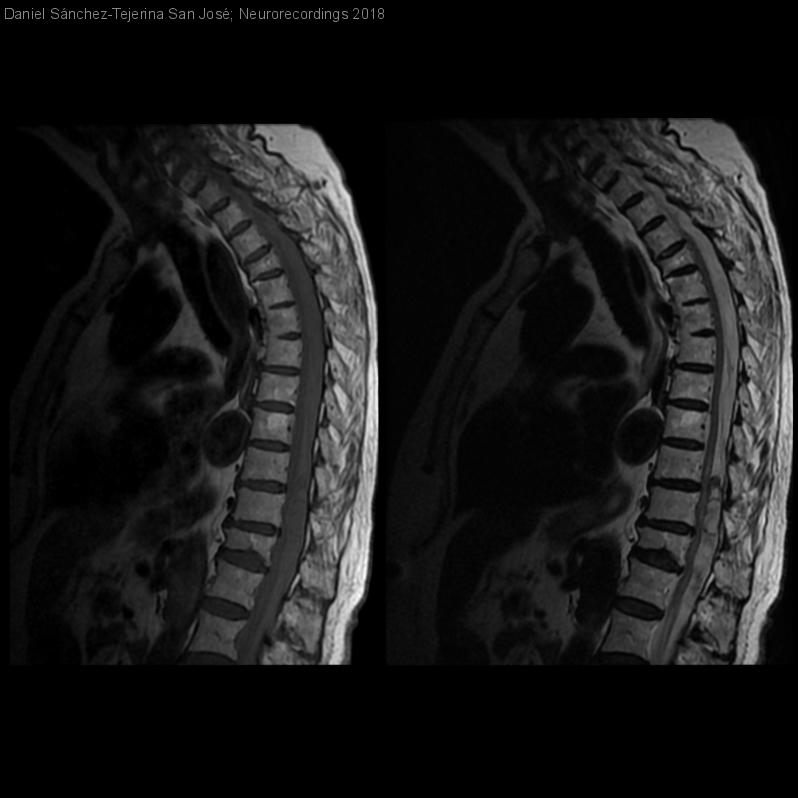

COMPRESIÓN MEDULAR SECUNDARIA A HEMATOMA ESPINAL SUBDURAL

Diagnóstico final: Síndrome medular completo secundario a hematoma espinal subdural de origen traumático